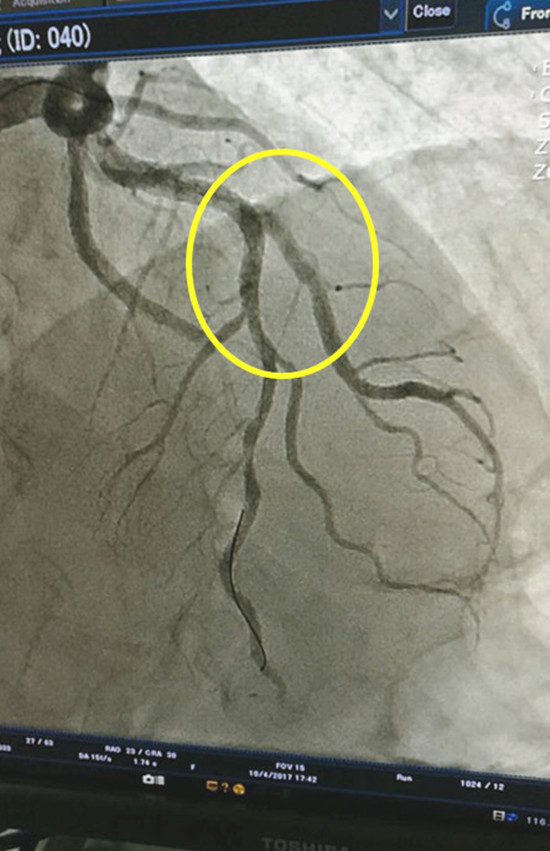

图2 介入治疗后患者血管恢复畅通

对于急性心梗患者来说,时间就是心肌,时间就是生命!经该院介入团队紧密协作,为李大爷实施了急诊冠脉造影术及冠脉支架植入术。造影检查显示,患者的前降支近中段严重狭窄达95%伴钙化及血栓。医院介入团队随即为他进行介入治疗,在血管狭窄处植入一个支架,将血管开通。患者胸痛立即得到了缓解,成功挽救了患者的生命。